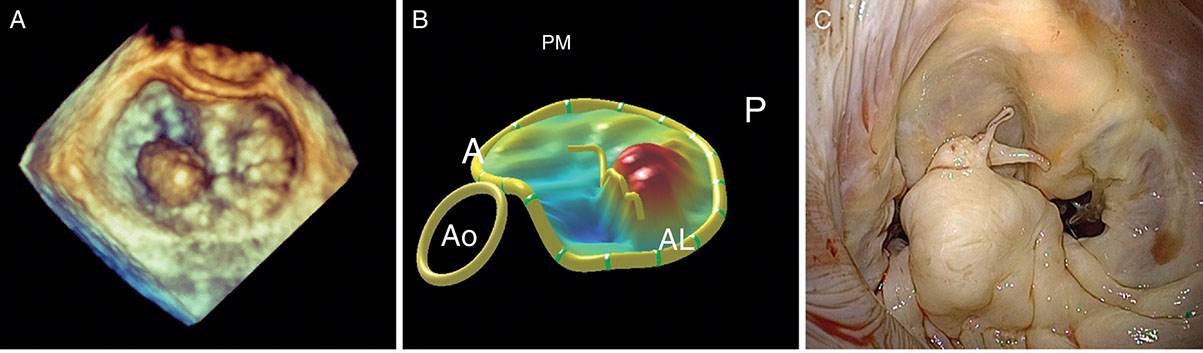

- Ecocardiograma Doppler 3D para paciente adulto y pediátrico. Es un examen que emplea ondas sonoras para crear una imagen en movimiento del corazón.